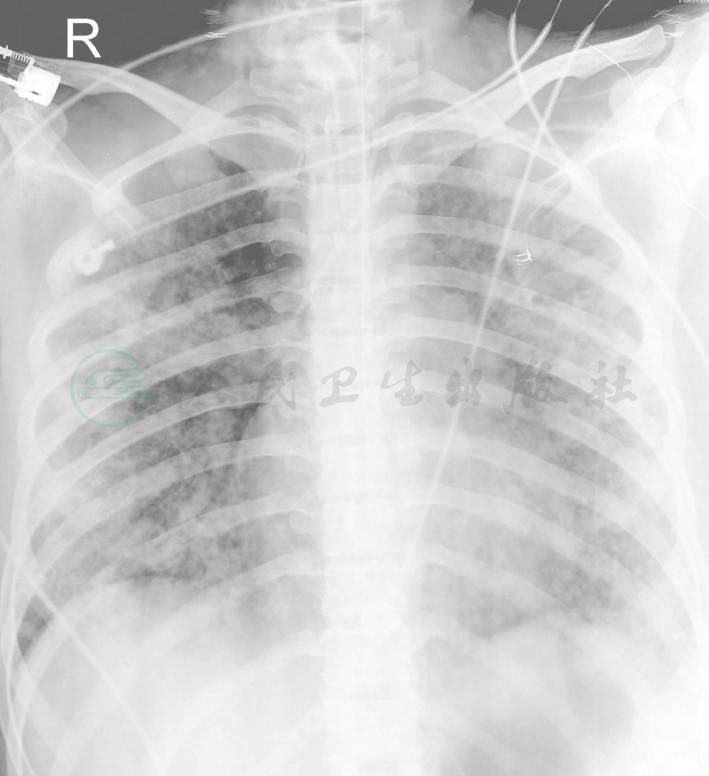

入院抽血培养后给予青霉素、头孢曲松抗感染、升白细胞及对症支持治疗。同时进行骨穿检查,结果显示骨髓类白血病反应可能性大,白血病不能排外。12月13日晚22:00时,患者出现高热,体温高达40℃,血压下降为60/30mmHg,心率140次/分,考虑感染性休克,给予补液扩容、多巴胺、间羟胺升压,改用亚胺培南/西司他丁抗感染治疗。患者于次日中午开始出现呼吸急促、胸闷、气短,经皮氧饱和度下降至77%,血气分析显示氧分压为45mmHg,床旁胸片提示两肺渗出影(图1)。给予无创呼吸机辅助呼吸,低氧血症未得到明显改善,呼吸频率高达70次/分。同时体检发现全身皮肤出现散在的红色结节,中央有脓点,血培养提示革兰阳性细菌生长,立即加用万古霉素联合亚胺培南/西司他丁治疗。同时取皮肤结节脓液送检培养。追问病史,患者发病前脸部痤疮感染并有过挤压。由于病情危重并迅速恶化,脓毒血症不能排外,经全院扩大会诊立即转入ICU诊治。

图1 12月13日胸部平片提示两肺弥漫性渗出影